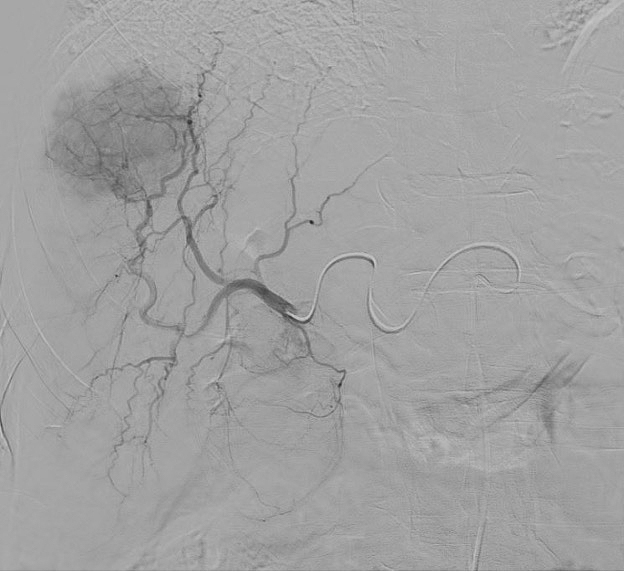

The Philips Azurion 7 C20 will allow us to provide top of the art diagnostic and therapeutic image guided procedures with lower radiation dose. Spacious rooms and special features will greatly improve patient satisfaction and will provide a safe environment for any complex intervention with ample space for anesthesiology.

Equipped with sophisticated advanced image-guidance systems and multi-imaging modalities, our physicians may now better visualize and treat patients with complicated diseases. This system includes technology to make this easier in both 2D and 3D with dose reduction technology. It is equipped with integrated Intravascular Ultrasound. Vessel Navigation guidance, 2D Vessel Perfusion, 3D roadmap and Vessel quantitative measurements are offered as well. Vessel Navigator allows reuse of 3D vascular anatomical information from existing CTA and MRA datasets as a 3D roadmap overlay on live X-ray images. With its sophisticated visualization, it provides an intuitive and continuous 3D roadmap to guide you through vasculature during the entire procedure. The system is connected to our PACS system allowing us to visualize previous diagnostic images inside the room.

As the clinician moves the system, the image beam automatically maintains alignment with the patient, allowing more consistent visualization and enabling them to keep their focus on the treatment. In addition, the room has ability to perform cone-beam XperCT, which will allow us to move some interventional procedures from one of the CT scanners on the first floor of University, further freeing-up capacity for diagnostic CT.